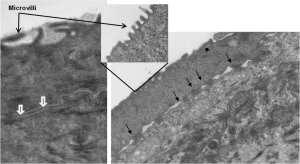

TEM Analysis of EpiCorneal illustrates the presence of 1) microvilli, 2) tight junctions (white arrows), and 3) desmosomes (black arrows). Image Credit: MatTek